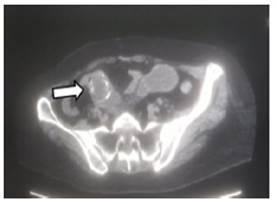

Una ecografía abdominal (Figura 2a), indica distensión de asas intestinales, compatible con una obstrucción intestinal; la tomografía de abdomen simple (Figura 2b), muestra un lito de más o menos 5 cm en intestino delgado, compatible con probable íleo biliar.

Figura 2b Tomografía de abdomen en la cual la flecha blanda indica presencia de lito, indicada por la flecha blanca.

Para el diagnóstico se solicitan estudios de imagen, como una radiografía de abdomen y en los hallazgos se busca la famosa tríada de Rigler, que consiste en la presencia de cálculos radiopacos (presentándose en menos del 10 % de los casos), neumobilia (signo de Gotta-Mentschler), y distensión de las asas intestinales; la presencia de 2 de los 3 signos establece el diagnóstico11; en nuestro caso se puede evidenciar claramente 2 criterios que son, presencia de lito y datos de distención intestinal. El estudio de preferencia es la tomografía de abdomen, la cual puede confirmar el diagnóstico, permitir localizar el sitio de obstrucción, determinar presencia de neumobilia, y planificar el tratamiento12; en el caso de nuestro paciente este examen claramente reflejo el diagnostico en mención.